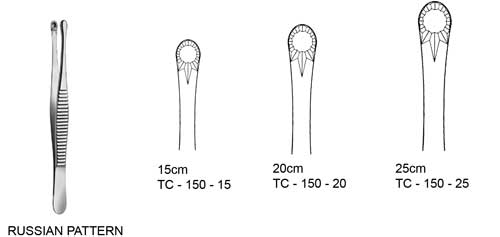

Kẹp phẫu tích của Nga thì có đầu tác dụng to, tròn, để kẹp mô nhưng chủ yếu thích hợp khi kẹp các mảnh gãy vỡ, ốc vis hoặc các dụng cụ khác. Ngoài ra còn được sử dụng để kẹp và đặt gạc vào trong miệng.